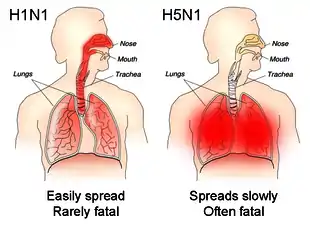

Influenza is usually transmissible from one day before the onset of symptoms to 5–7 days after.[9] In healthy adults, the virus is shed for up to 3–5 days. In children and the immunocompromised, the virus may be transmissible for several weeks.[8] Children ages 2–17 are considered to be the primary and most efficient spreaders of influenza.[1][9] Children who have not had multiple prior exposures to influenza viruses shed the virus at greater quantities and for a longer duration than other children.[1] People who are at risk of exposure to influenza include health care workers, social care workers, and those who live with or care for people vulnerable to influenza. In long-term care facilities, the flu can spread rapidly after it is introduced.[9] A variety of factors likely encourage influenza transmission, including lower temperature, lower absolute and relative humidity, less ultraviolet radiation from the Sun,[26][28] and crowding.[25] Influenza viruses that infect the upper respiratory tract like H1N1 tend to be more mild but more transmissible, whereas those that infect the lower respiratory tract like H5N1 tend to cause more severe illness but are less contagious.[8]